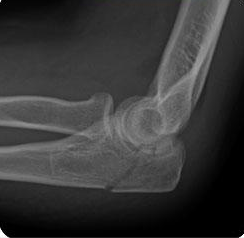

hvilken skade mistenker du ved disse kliniske funnene:

Skade på caput eller collum radii. Må mistenke fraktur. Ta rtg. evt. CT for å kartlegge step i leddflaten.